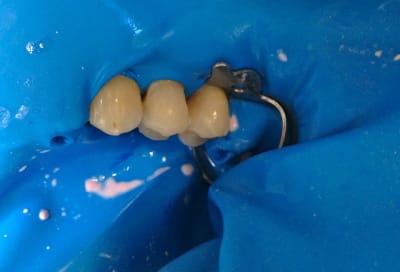

Alors comment traiteriez vous cette 24 asymptotique, qui présente un enorme délabrement sous gingival , notez que l'émail n'est plus soutenu par la dentine à aucun endroit ?

1ère séance remontées de la marche distale au compo flow + compo de restauration / réalisation d'un IDS , le tout sous digue bien sur (voir radio jointe , désolé à l'envers))

Voici les photos toutes fraiches de ce matin.

Vos critiques sont bien sur les bienvenues je dois encore beaucoup m'améliorer sur les prises de teintes, et je m'y attelle en ce moment,, par contre en ce qui concerne la pérennité de la restauration…..ma patiente a sa dent bien vivante, aucun joint sous gingival , possibilité de réaliser une endo dans le futur sans détruire la restauration existante si besoin, possibilité re refaire un onlay dans quelques années si ça casse, toujours sur dent vivante…. bref la liste des avantages est très longue par rapport au classique endo-IC-CCM.